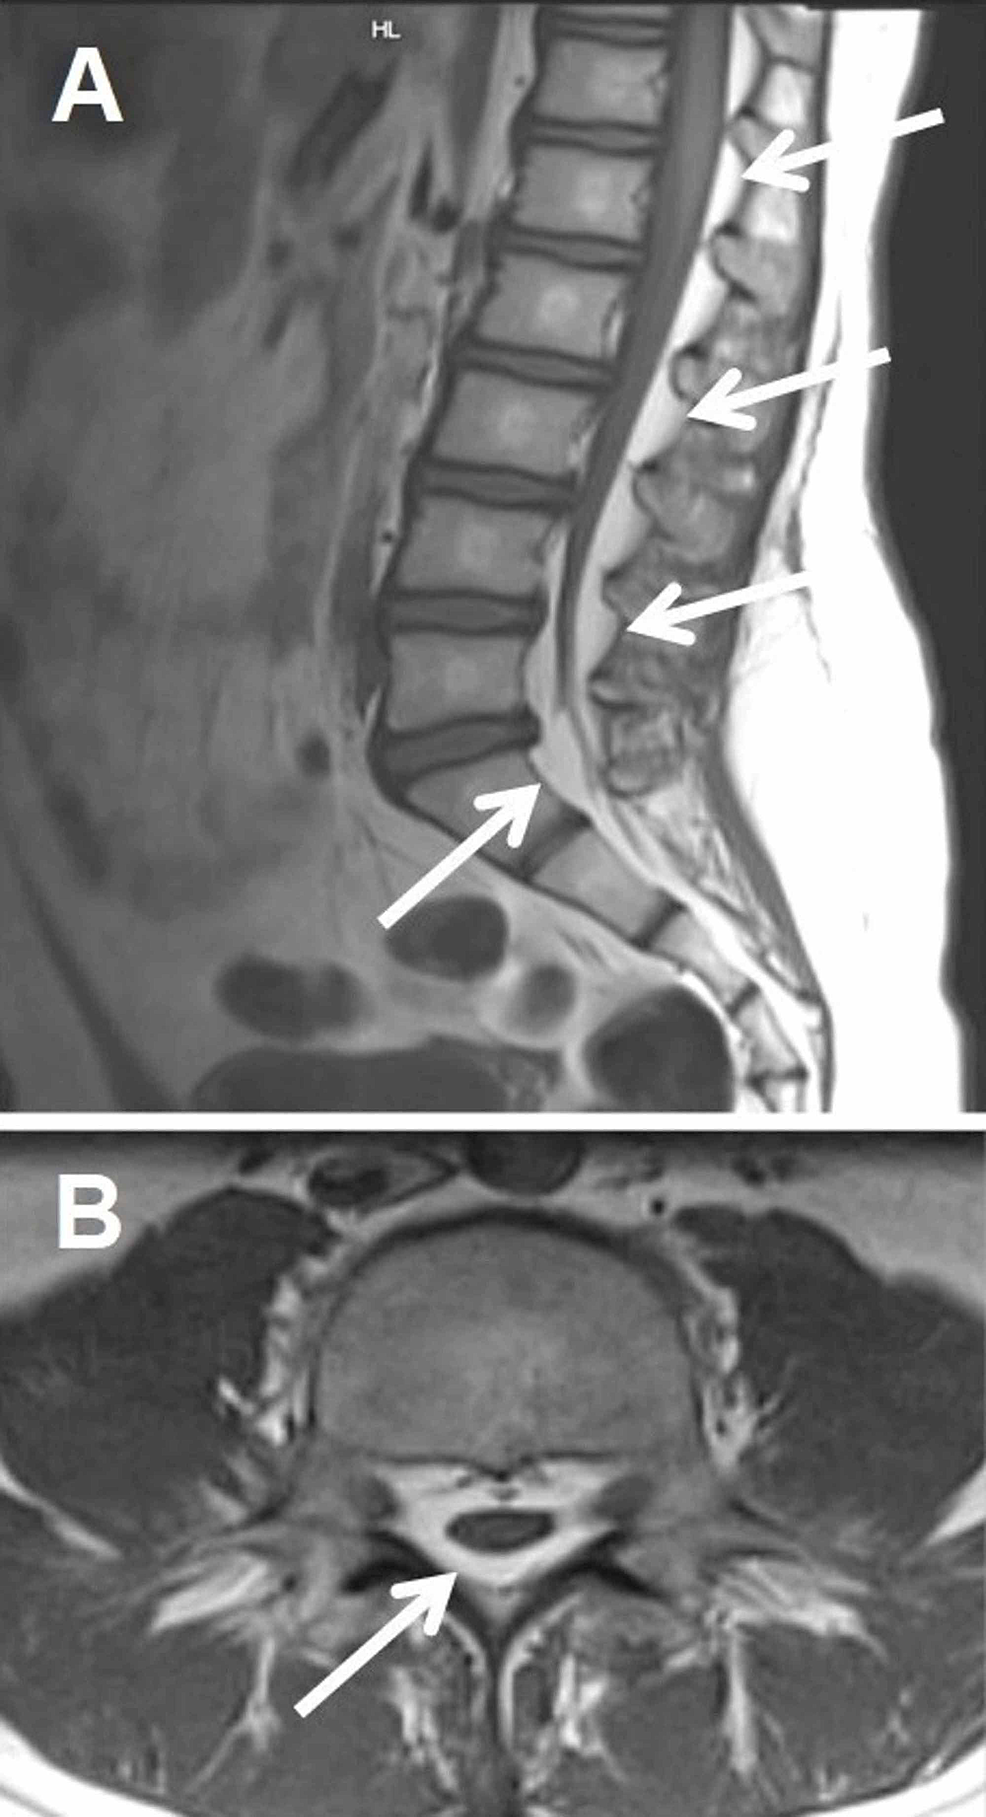

spinal dural AVF

present with gradual but progressive pain, leg weakness/numbness, bladder/bowel changes

flow voids on T2

can see intramedullary hyperintensity due to edema, often involving conus

confirmed with DSA